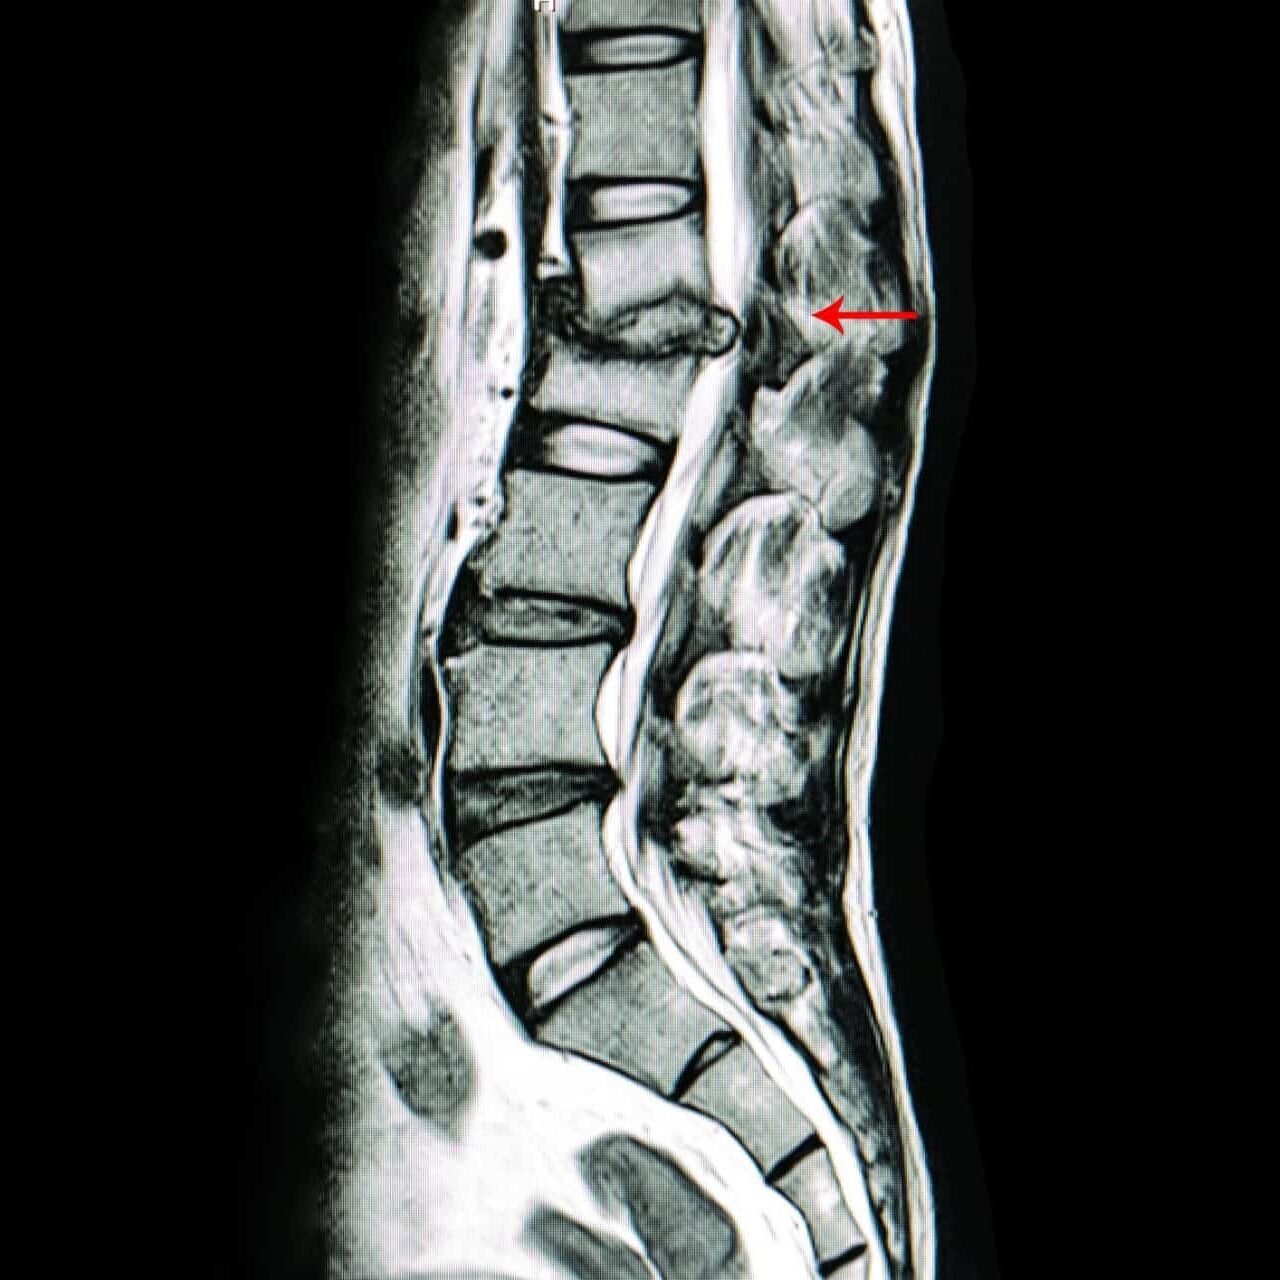

Was passiert bei einem Bandscheibenvorfall?

Ein Bandscheibenvorfall tritt auf, wenn der Gallertkern einer Bandscheibe durch den Faserring austritt und auf umliegende Nerven drückt. Das kann zu Schmerzen, Taubheitsgefühlen oder sogar Lähmungen führen.

Interessanterweise zeigen bildgebende Verfahren oft Bandscheibenvorfälle bei Menschen, die gar keine Symptome haben. Diese "Zufallsbefunde" treten in etwa 30% der Fälle auf (Brinjikji et al., 2015).